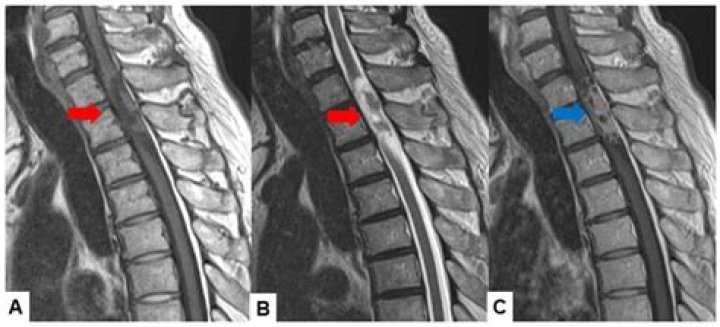

Spinal magnetic resonance imaging (MRI).

MRI is usually the preferred test to diagnose tumors of the spinal cord and surrounding tissues. A contrast agent that helps highlight certain tissues and structures may be injected into a vein in your hand or forearm during the test.